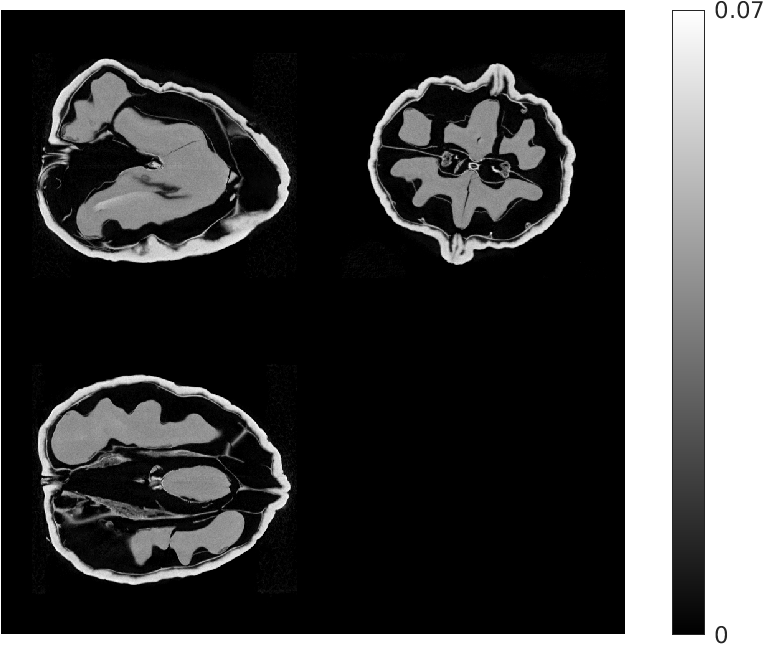

Fig. 3 compares the reconstructions from 4 views. The quality of the reconstruction is poorer compared to that using 8 views, though the proposed approach still visibly outperforms the other methods.

| Ground Truth Test Volume | |

![]() |

|

| (a) (NMAE) | |

| FDK | EP Regularized Recon. |

| (b) (1.23) | (c) (0.65) |

| Destreaking CNN | Proposed |

| (d) (0.63) | (e) (0.45) |